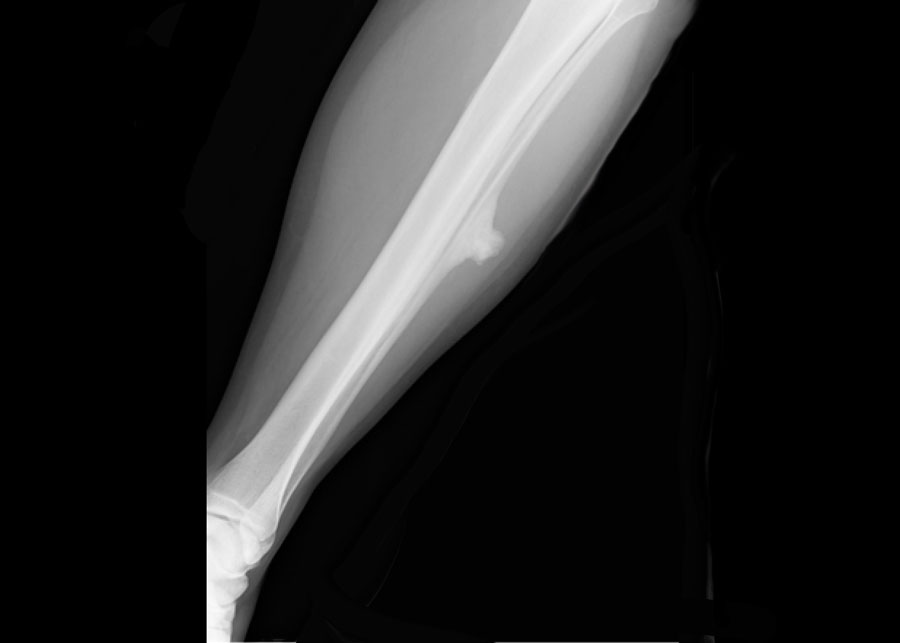

Here images of a 30-year-old male.

There is a wel-defined lytic lesion of the olecranon with several ridges and a pathologic fracture.

The differential diagnosis includes giant cell tumor and ABC.

The T2WI+FS shows fluid-levels due to sedimentation making ABC the most likely diagnosis.

Biopsy however revealed Brown tumor.